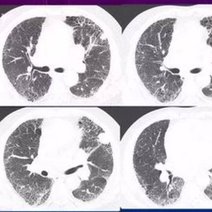

白肺的意思是指胸片、CT上发现正常肺组织透X线是黑色,只有心脏和大血管是白色,但是由于各种疾病、各种致病因素,导致两肺野呈大片的密度增高,出现白色的阴影,就...47600人收听

白肺一般是指重症肺炎在X光检查下的表现,肺部呈现一大片的白色状态而闻名。形成白肺一般都预示着肺部被炎症所广泛浸润,引起白肺的病因往往非常复杂,并且来势凶...28117人收听

白肺是指患者在X光胸片检查或者肺部CT检查中,肺部间质组织呈现大片状白色状病变的表现。白肺的症状表现多发生于重症肺炎,因为肺部间质组织持续性受到病毒、细...60057人收听

白肺(White lung)是一种临床综合症,其特征是重度肺炎患者的肺部积累了大量渗出物,影响多个肺叶,使肺部影像学检查呈现出大范围的白色区域。病因多为新型冠状病毒感染、细菌性肺炎、中东呼吸...

[最佳答案] 白肺是放射学名词,所谓白肺是指胸片或者CT上弥漫的高密度影,使得片子看不到肺纹理。导致白肺发生的原因很多,常见的大叶性肺炎、肺水肿,或者是病毒性肺炎比如SARS,以及流感、病毒引起的肺炎都会导致白肺。 至于能不能治愈要根据疾病的不同来决定, 白肺是放射学名词,所谓白肺是指胸片或者CT上弥漫的高密度影,使得片子看不到肺...